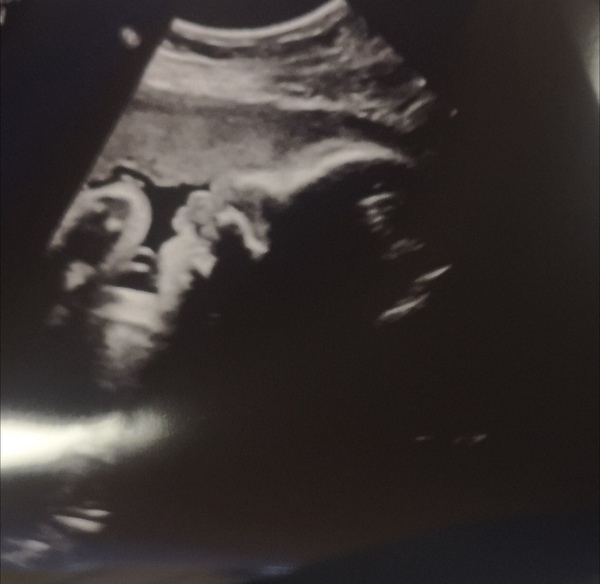

I managed to get another hours sleep and have been for my growth scan. Everything is still looking good, now about 5lb 14 and in the right position. Consultant has confirmed that I'll be offered an indication from 40+7 if I go over (I'm hoping I won't 😂) goblin is looking really good, head was right down but we still managed a picture.

Whoops managed to cross post on the list and forget to add the picture 🙈